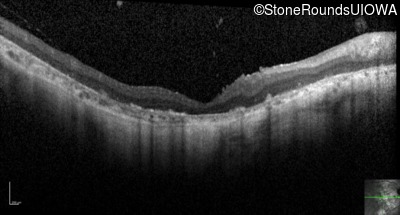

Optical Coherence Tomography - Right - Hand Motion sc

Exemplar / OCT Stack